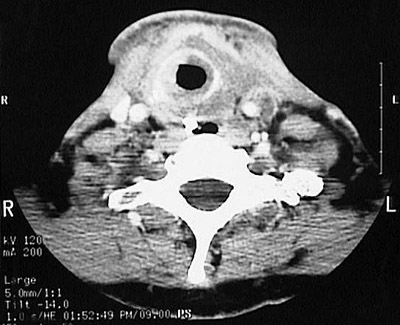

This axial head CT scan demonstrates an ill-defined infiltrative mass of the thyroid, consistent with an anaplastic carcinoma.